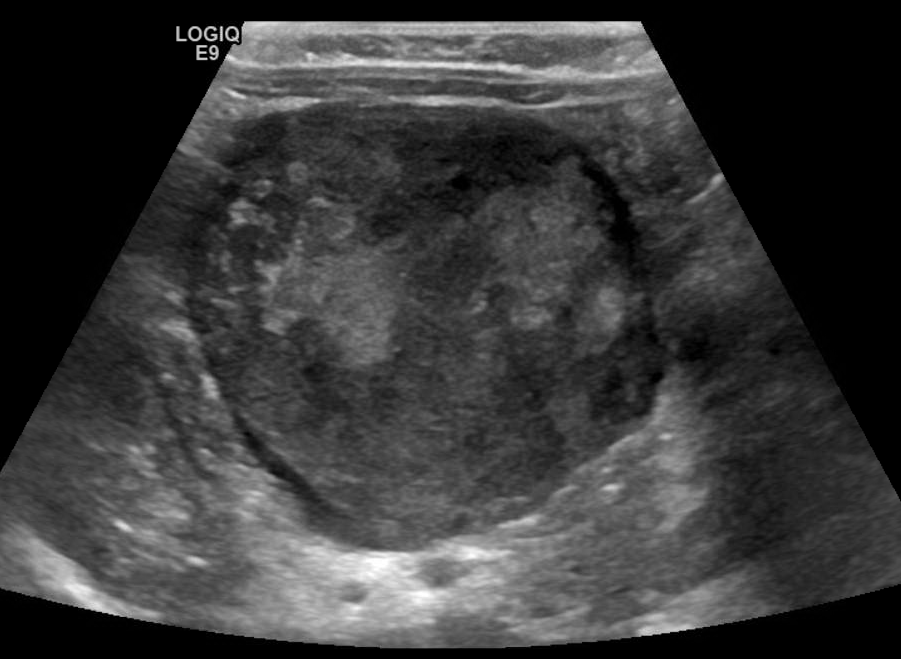

Ultrasound appearance

On ultrasound you may encounter a round or ovoid mass with mixed echogenicity often time does the punctate echogenic foci representing classifications.

Retroperitoneal Neuroblastoma